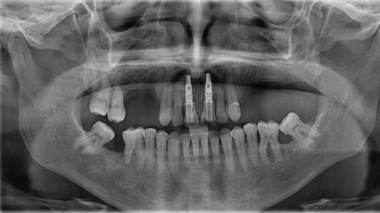

Posteriormente se realizó una impresión de alginato y vaciado en yeso del maxilar, se eliminaron mecánicamente ambos incisivos centrales. Este modelo se digitalizó con un escáner extraoral (3Shape, Trios) y se obtuvo un archivo STL. Luego con esto datos se hizo una coincidencia digital entre el CBCT y el archivo STL, utilizando el software BlueSky plan, (BlueSky bio). Se planificaron dos implantes cónicos de conexión interna de 3.8 x12 mm (Biohorizons), separados de la parte vestibular de las raíces y asegurando su correcto posicionamiento implantario (Img 1). Luego se diseñó una guía quirúrgica en el mismo software, exportada e impresa en ácido poliláctico (PLA) por una impresora de tecnología de deposición de material fundido (FDM) (Duplicator 7, Wanhao, China). Después de la anestesia local, se extrajo la porción coronal de ambos dientes fracturados, luego las partes apicales restantes se dividieron mesio-distalmente con una fresa de diamante de alta velocidad dejando dos porciones. Se retiró la parte palatina y se conservaron 5 mm de la pared vestibular radicular, posteriormente se instaló la guía quirúrgica en posición (Fig 2 y 3).

Después de la cirugía, ambas coronas naturales se adaptaron para ajustarse a un pilar temporal de titanio. Utilizando el adhesivo Universal (3M ESPE) y cementadas con resina fluida (A2 3M ESPE), siguiendo el protocolo de adhesión del fabricante, se confeccionaron las coronas provisionales, las que fueron instaladas como provisorios inmediatos en los implantes en boca, fue citado a control post operatorio, donde se tomó Radiografía panorámica (Img 2). Dándose de alta 21 días post intervención. Se hizo seguimientos a los seis y doce meses posteriores al alta.